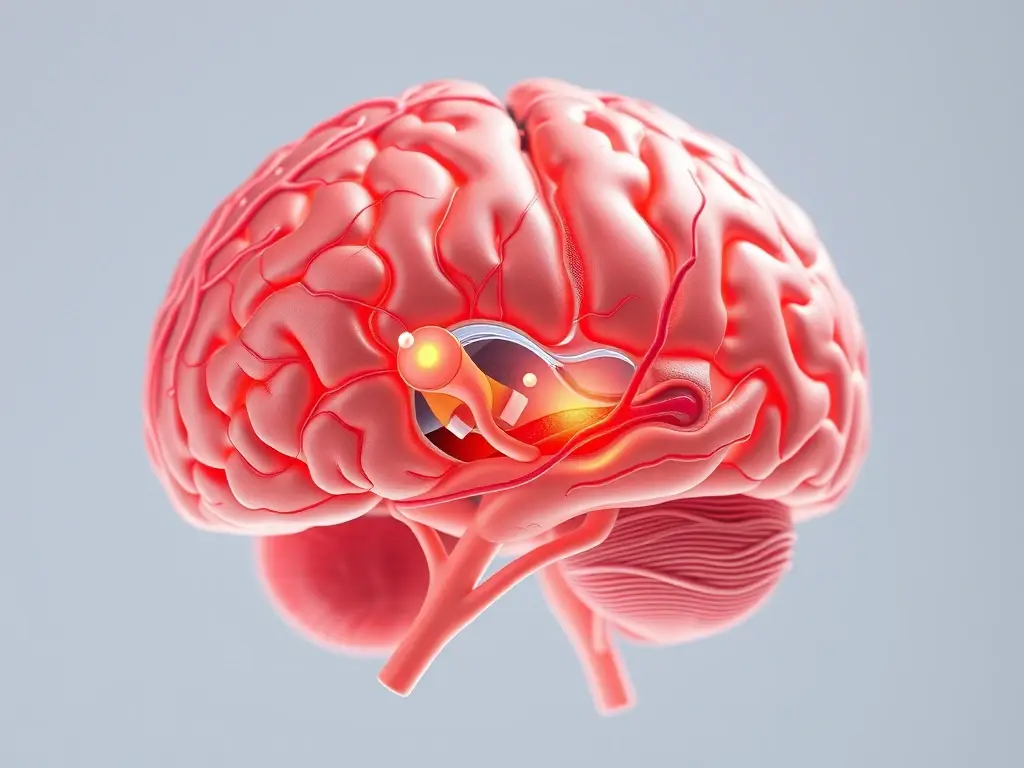

Es importante destacar que el síndrome vestibular no es una enfermedad en sí misma, sino más bien un conjunto de signos clínicos que indican una disfunción en el sistema vestibular. Este sistema, complejo y vital, incluye el oído interno, los nervios que conectan el oído con el cerebro, y las áreas del cerebro que procesan la información relacionada con el equilibrio. Cuando algo interfiere con el funcionamiento correcto de alguna de estas partes, el resultado es la pérdida de equilibrio, la inclinación de la cabeza y otros síntomas que observamos en los conejo mareado. Comprender la raíz del problema es fundamental para brindarle a nuestro conejo la atención adecuada y mejorar su calidad de vida.

El sistema vestibular es el encargado de mantener el equilibrio, la postura y la orientación espacial en todos los animales, incluyendo a los conejos. Imaginen un sofisticado sistema de sensores que constantemente recopila información sobre el movimiento de la cabeza y el cuerpo, y la transmite al cerebro para que pueda ajustar la postura y mantenernos estables. Este sistema está ubicado principalmente en el oído interno, donde se encuentran estructuras llenas de líquido que detectan los cambios en la posición de la cabeza y la aceleración. Los impulsos generados por estos sensores viajan a través de nervios hasta el cerebro, donde se integran con la información proveniente de la vista y la propiocepción (la percepción del cuerpo en el espacio).

Este proceso, aparentemente simple, es en realidad un trabajo de equipo complejo que involucra a varios componentes del sistema nervioso. Cuando la información proveniente del oído interno, la vista y la propiocepción coincide, el cerebro puede mantener el equilibrio y la postura de manera precisa. Sin embargo, cuando hay una discrepancia entre estas fuentes de información, como ocurre en el síndrome vestibular, se producen los síntomas que observamos en los conejos afectados. Entender cómo funciona este sistema y los componentes que lo integran es esencial para comprender las causas y los mecanismos subyacentes al síndrome vestibular en conejos.